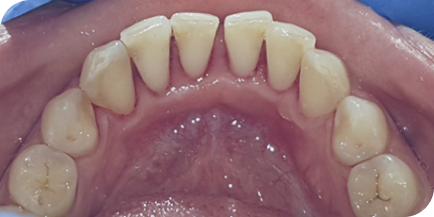

Случай из практики.

Наращивание десны

Часто наши пациенты спрашивают, через какое время после наращивания десна снова опустится вниз. С уверенностью могу сказать, что при соблюдении всех рекомендаций зубы, которые были уже на грани удаления, будут служить пациенту всю жизнь!

Пациентку (Екатерина, 55 лет) в нашу клинику отправили из другой клиники наши коллеги. Цель — вылечить и нарастить десну перед протезированием зубов.

Это был непростой клинический случай с наращиванием десны

в эстетически значимой зоне.

На фотографиях исходное состояние, состояние спустя год после наращивания и 5 лет после наращивания. Результат стабилен.

Десна после наращивания никогда не опустится, если пациент соблюдает все рекомендации врача: приходить на регулярные профилактические осмотры.